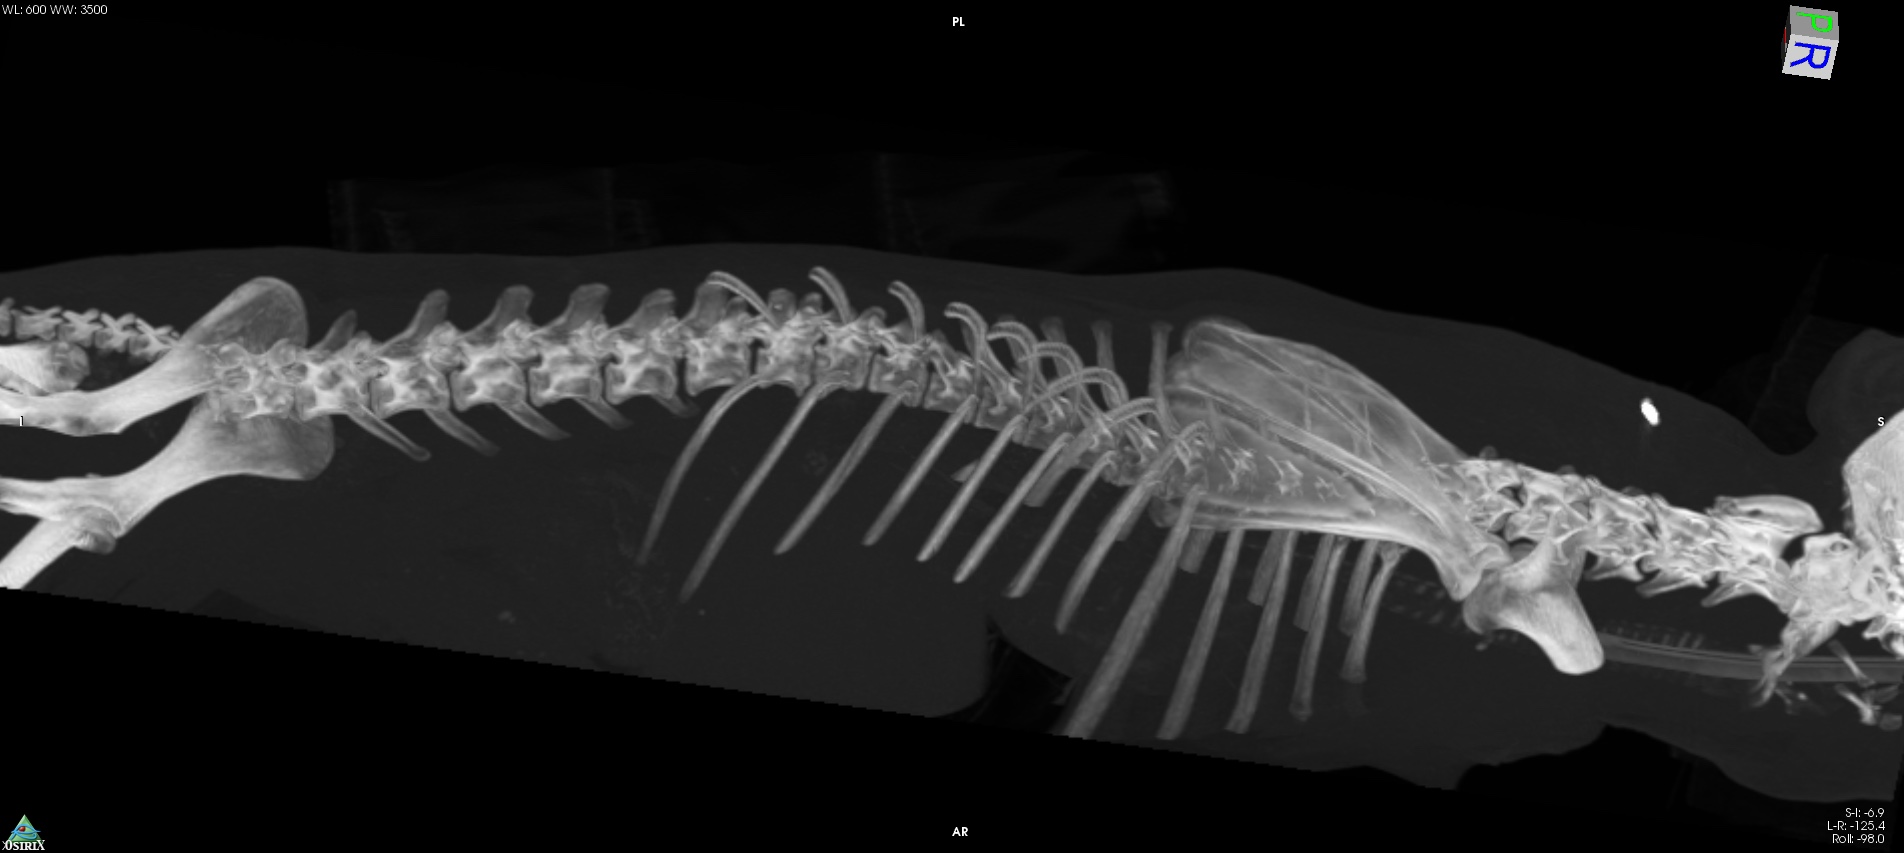

Scanner de colonne vertébrale de chien au centre d'imagerie Scanvet Lyon Scanner Chien Manage Scanner destinés aux chiens, aux chats, lapins, furets, rats, reptiles et tous les oiseaux (rapaces, poules, perroquets, etc.). Principe, indications, risques et tarifs du scanner. Le prix pour passer un scanner pour chien peut varier en fonction de plusieurs facteurs, notamment la localisation géographique, le type. Technique d’imagerie médicale utilisée en médecine vétérinaire, le scanner est utile pour diagnostiquer diverses. Scanner Chien Manage.

Le prix pour passer un scanner pour chien peut varier en fonction de plusieurs facteurs, notamment la localisation géographique, le type. Comment se déroule l’examen ? Technique d’imagerie médicale utilisée en médecine vétérinaire, le scanner est utile pour diagnostiquer diverses maladies du chien. Le centre vétérinaire brasseur à manage offre des soins dédiés aux chiens, chats et nac. En belgique, les endroits où un animal peut bénéficier de ce service de pointe se comptent sur les doigts de la main. Pictavet imagerie met à votre disposition un site uniquement dédié à cet. Une association de vétérinaires de proximité vous propose une offre de services de diagnostic innovante et précise. Scanner destinés aux chiens, aux chats, lapins, furets, rats, reptiles et tous les oiseaux (rapaces, poules, perroquets, etc.). Le scanner est un moyen d’imagerie médical qui utilise les rayons x et qui permet des reconstructions informatiques en 2d et en 3d. Il fait partie de l’imagerie en coupe.